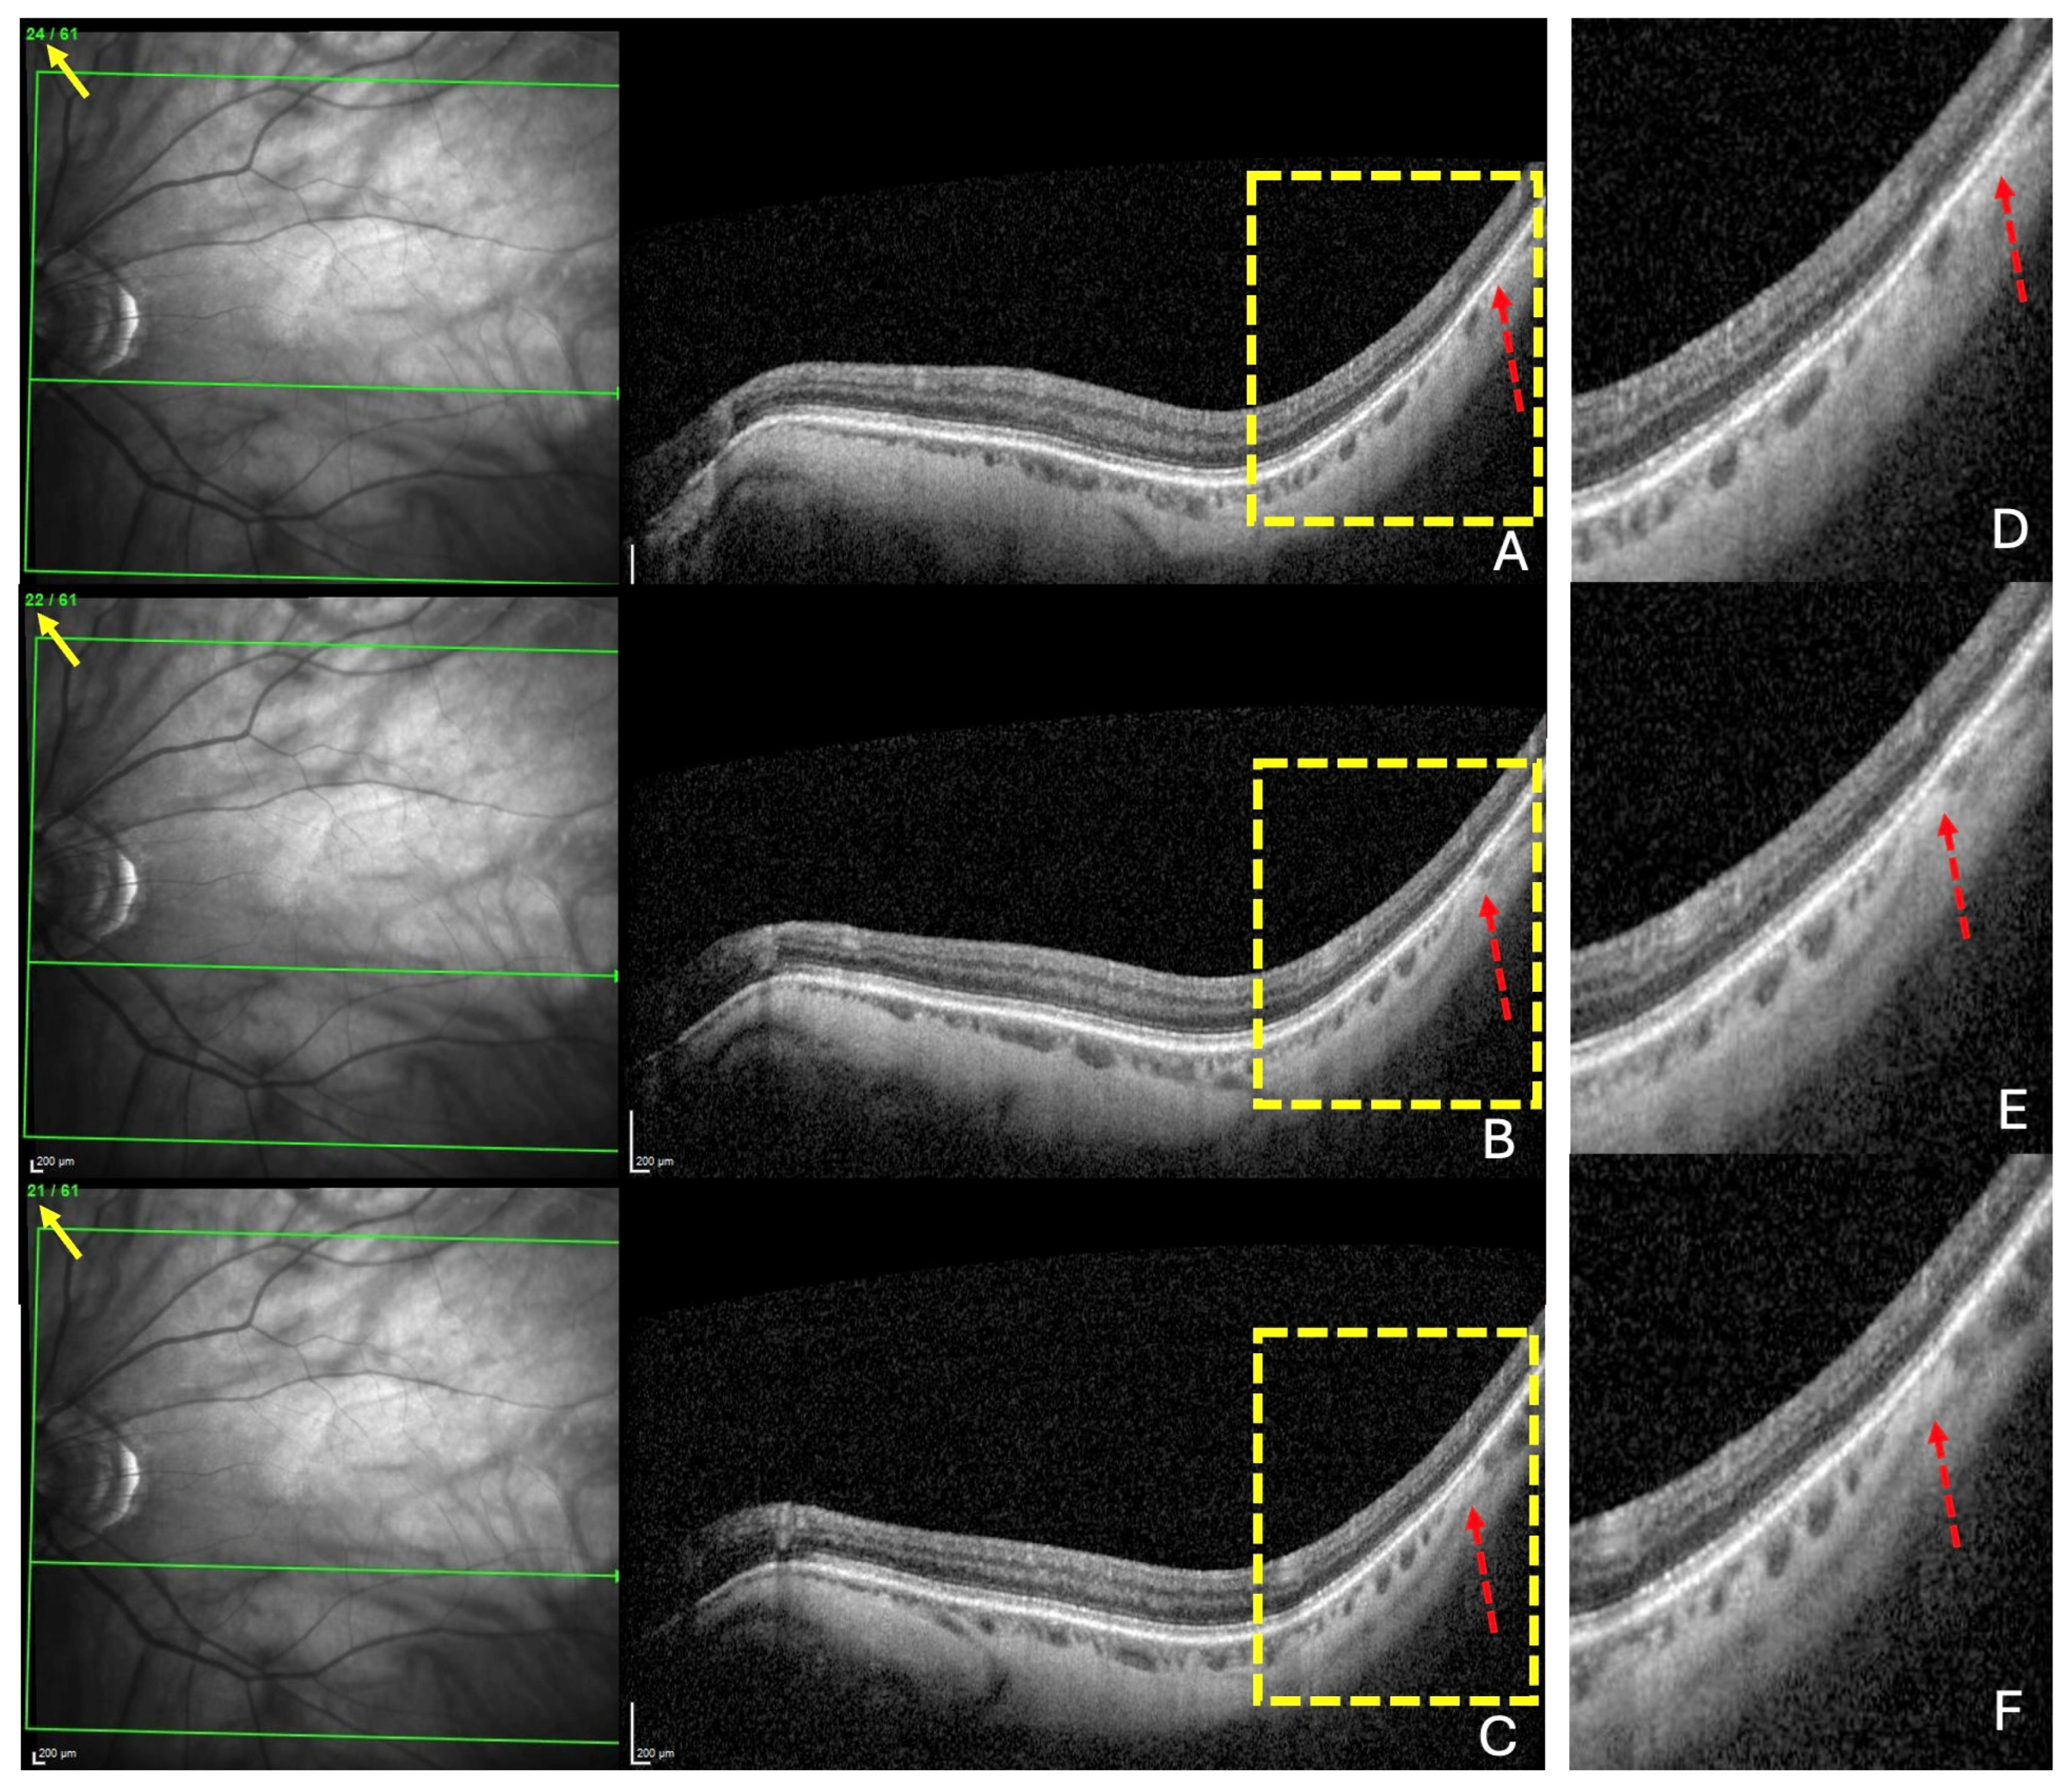

For each of the three locations, choroidal thinning was considered present when the thinning was noted in at least three adjacent sections (Figure 2A–C), emphasized in (Figure 2D–F).

Figure 2.

The diagnosis of a choroidal thinning within the band centered by the fovea–Bruch’s membrane opening axis. This diagnosis was retained if a thinning was noted in at least three consecutive sections (dashed red arrows) in (A–C). Section numbers are highlighted by the yellow arrows in (A–C). The green lines in (A–C) locate the corresponding OCT slices. The yellow rectangles in (A–C) are presented in (D–F), respectively.